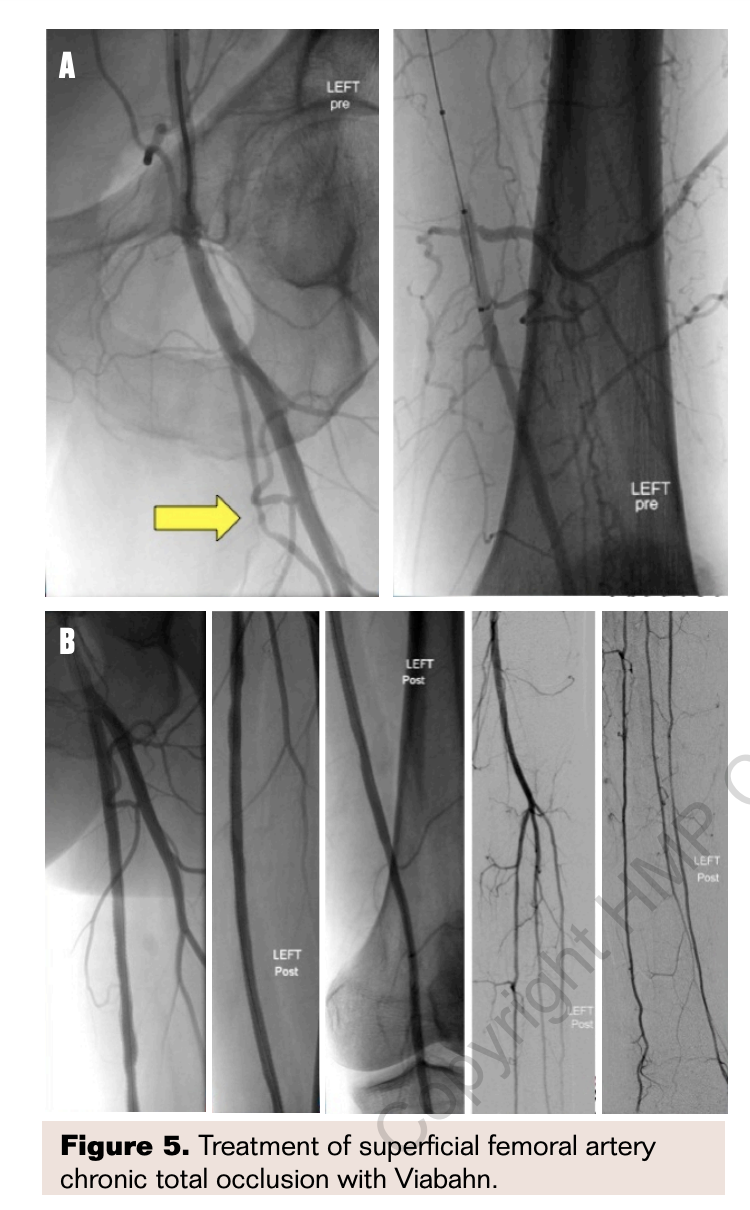

Chronic total occlusions were common (67%) and a lumen re-entry device was utilized in 43% of procedures. One-third of patients were being treated for severe stent restenosis or occlusion. Although lesion length was not measured, the average length of Viabahn endografts deployed was 34.9±9.7 cm. Angiograms from a typical procedure before and after Viabahn stenting are shown in Figure 5. Mean length of follow-up was just over 2 years. Primary patency was 71.8% with secondary patency of 90.5% at 27.8±9.5 months. Baseline and follow-up Ankle Brachial Index (ABI) was available in 25 patients showing improvement in ABI from 0.52±0.16 to 0.83±0.22 (P<.0001).